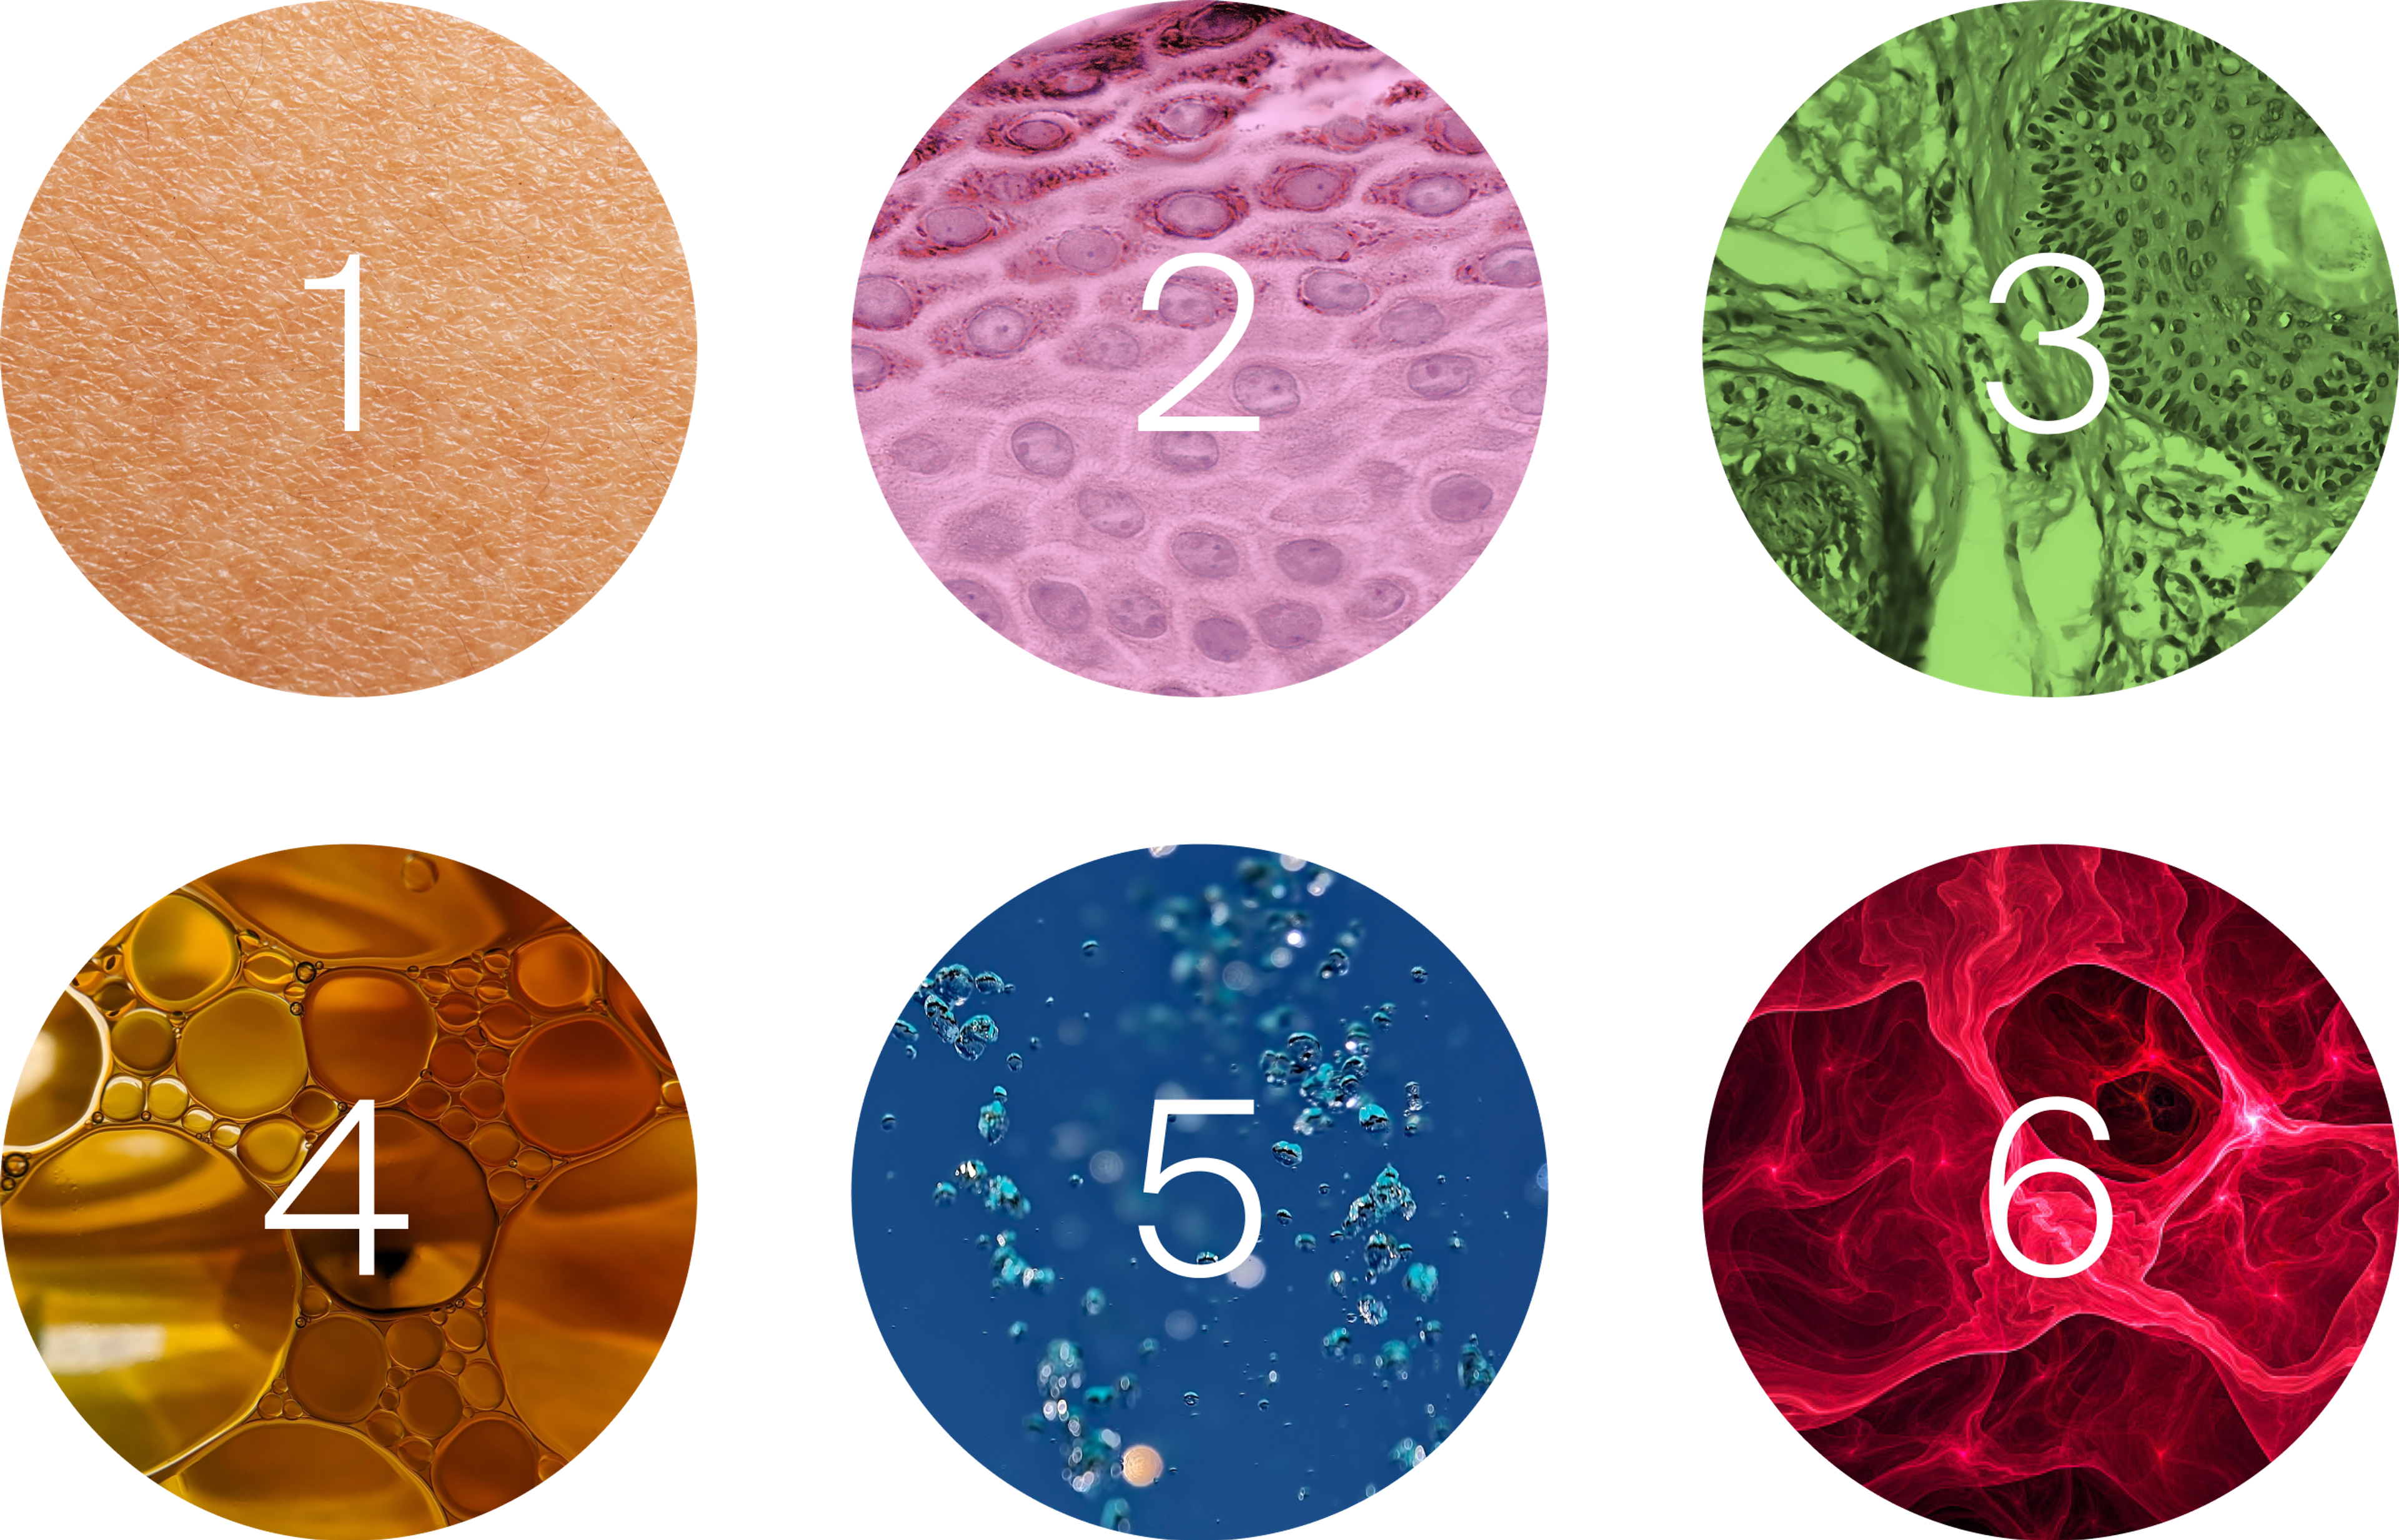

Our skin is composed of 3 layers of specialized cells. As we age, these cells become less efficient at producing energy to fuel their specific functions, eventually leading to signs of aging:[7]

1. The epidermis is mainly composed of keratinocytes that impart strength and drive skin cell renewal, and melanocytes which produce melanin. As we age, the aging keratinocytes are less able to maintain a strong skin barrier and the melanocytes’ melanin production becomes less even, leading to dark spots.

2. The dermis is made up of fibroblasts which produce collagen and elastin giving the skin its thickness and elasticity. As our cells age, fibroblasts produce less collagen and elastin leading to thinner more fragile skin.

3. The hypodermis is made up of adipocytes or fat cells and is the bottom layer of the skin. It protects the body from injury, is a very powerful insulator, and is rich in connective tissue, connecting the skin to the muscle. As we age, the hypodermis becomes thinner and less connective tissue is available to link the skin to the muscle, contributing to skin sagging.

The mighty mitochondria: The mitochondria are the powerhouse inside our cell. Scientists believe they may hold the key to longevity. They control the life and death of the cell (cellular renewal). Mitochondria need renewal and replacement themselves over time. This process is called mitophagy. Mitophagy is very important for cellular renewal.

Cell renewal in the body, including skin cell renewal, is regulated by the mitochondria inside the cell.[8] As the mitochondria become “worn”, new ones are needed. If new mitochondria can be efficiently replaced, our cells will be renewed and remain healthy and resilient. However, as we age the cell renewal of our keratinocytes becomes less efficient. This reduces the capacity of our skin cells to maintain and repair the protective barrier and leads to skin thinning, water loss, and poor wound healing. We also have fewer melanocytes as we age, leading to uneven pigmentation and age spots. Finally, fibroblasts produce less collagen and elastin, causing the skin to lose its thickness and elasticity.